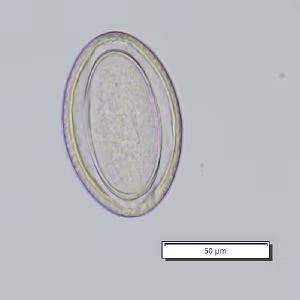

A 3-year-old boy was seen by a pediatrician for gastrointestinal pain and watery diarrhea. His parents conveyed that he has a propensity for putting insects in his mouth and sometimes eating them. A stool specimen was collected and processed for ova and parasites (O&P). A formalin-ethyl acetate (FEA) concentration was performed and a wet mount smear was prepared from the sediment and examined. Figures A and B show one parasite-like object at different focal planes at 200x magnification; another object from the sample is shown in Figures C and D, also at different focal planes, at 200x magnification. What is your diagnosis? Based on what criteria?

Figure C